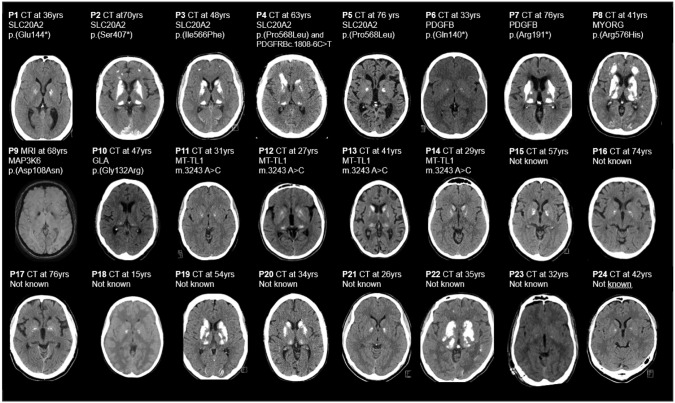

Results: Twenty-four families with BGCs and neurological symptoms were analyzed. Disease-causing variants were identified in 14 families (58.3%). Eight patients had IBGC (variants in SLC20A2, PDGFB, MYORG), 4 had mitochondrial disease (MT-TL1), and 2 had monogenic vascular conditions (GAL, MAP3K6). Three variants were novel. BGC severity was highest in IBGC cases, while vascular and mitochondrial cases had milder calcifications. White matter hyperintensities were seen in 94.7% of cases and correlated highly with the total calcification score. Clinical vascular events had occurred in 41.7% cases. No monogenic cause was found in 10 patients, although many of these showed clinical or radiological features suggestive of monogenic disease.